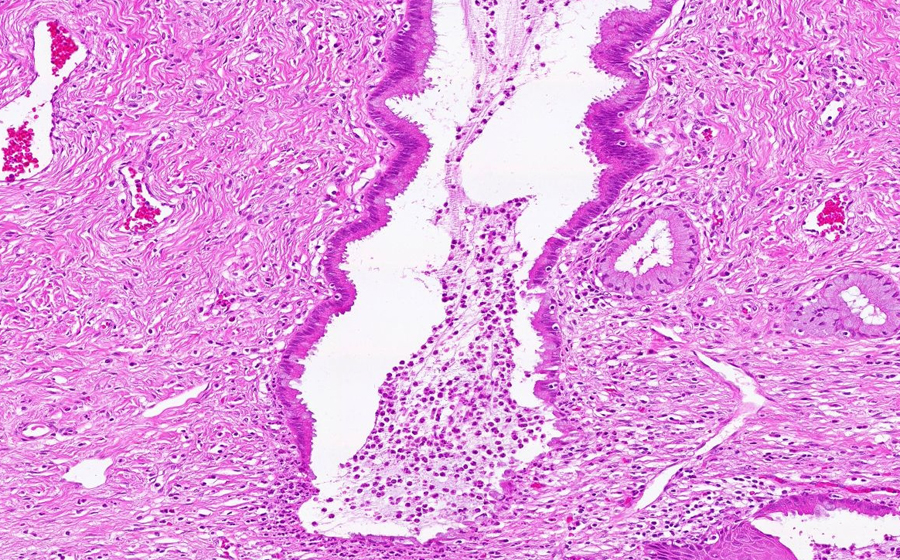

Image 2 - 50X

Slide 3 - Image 2